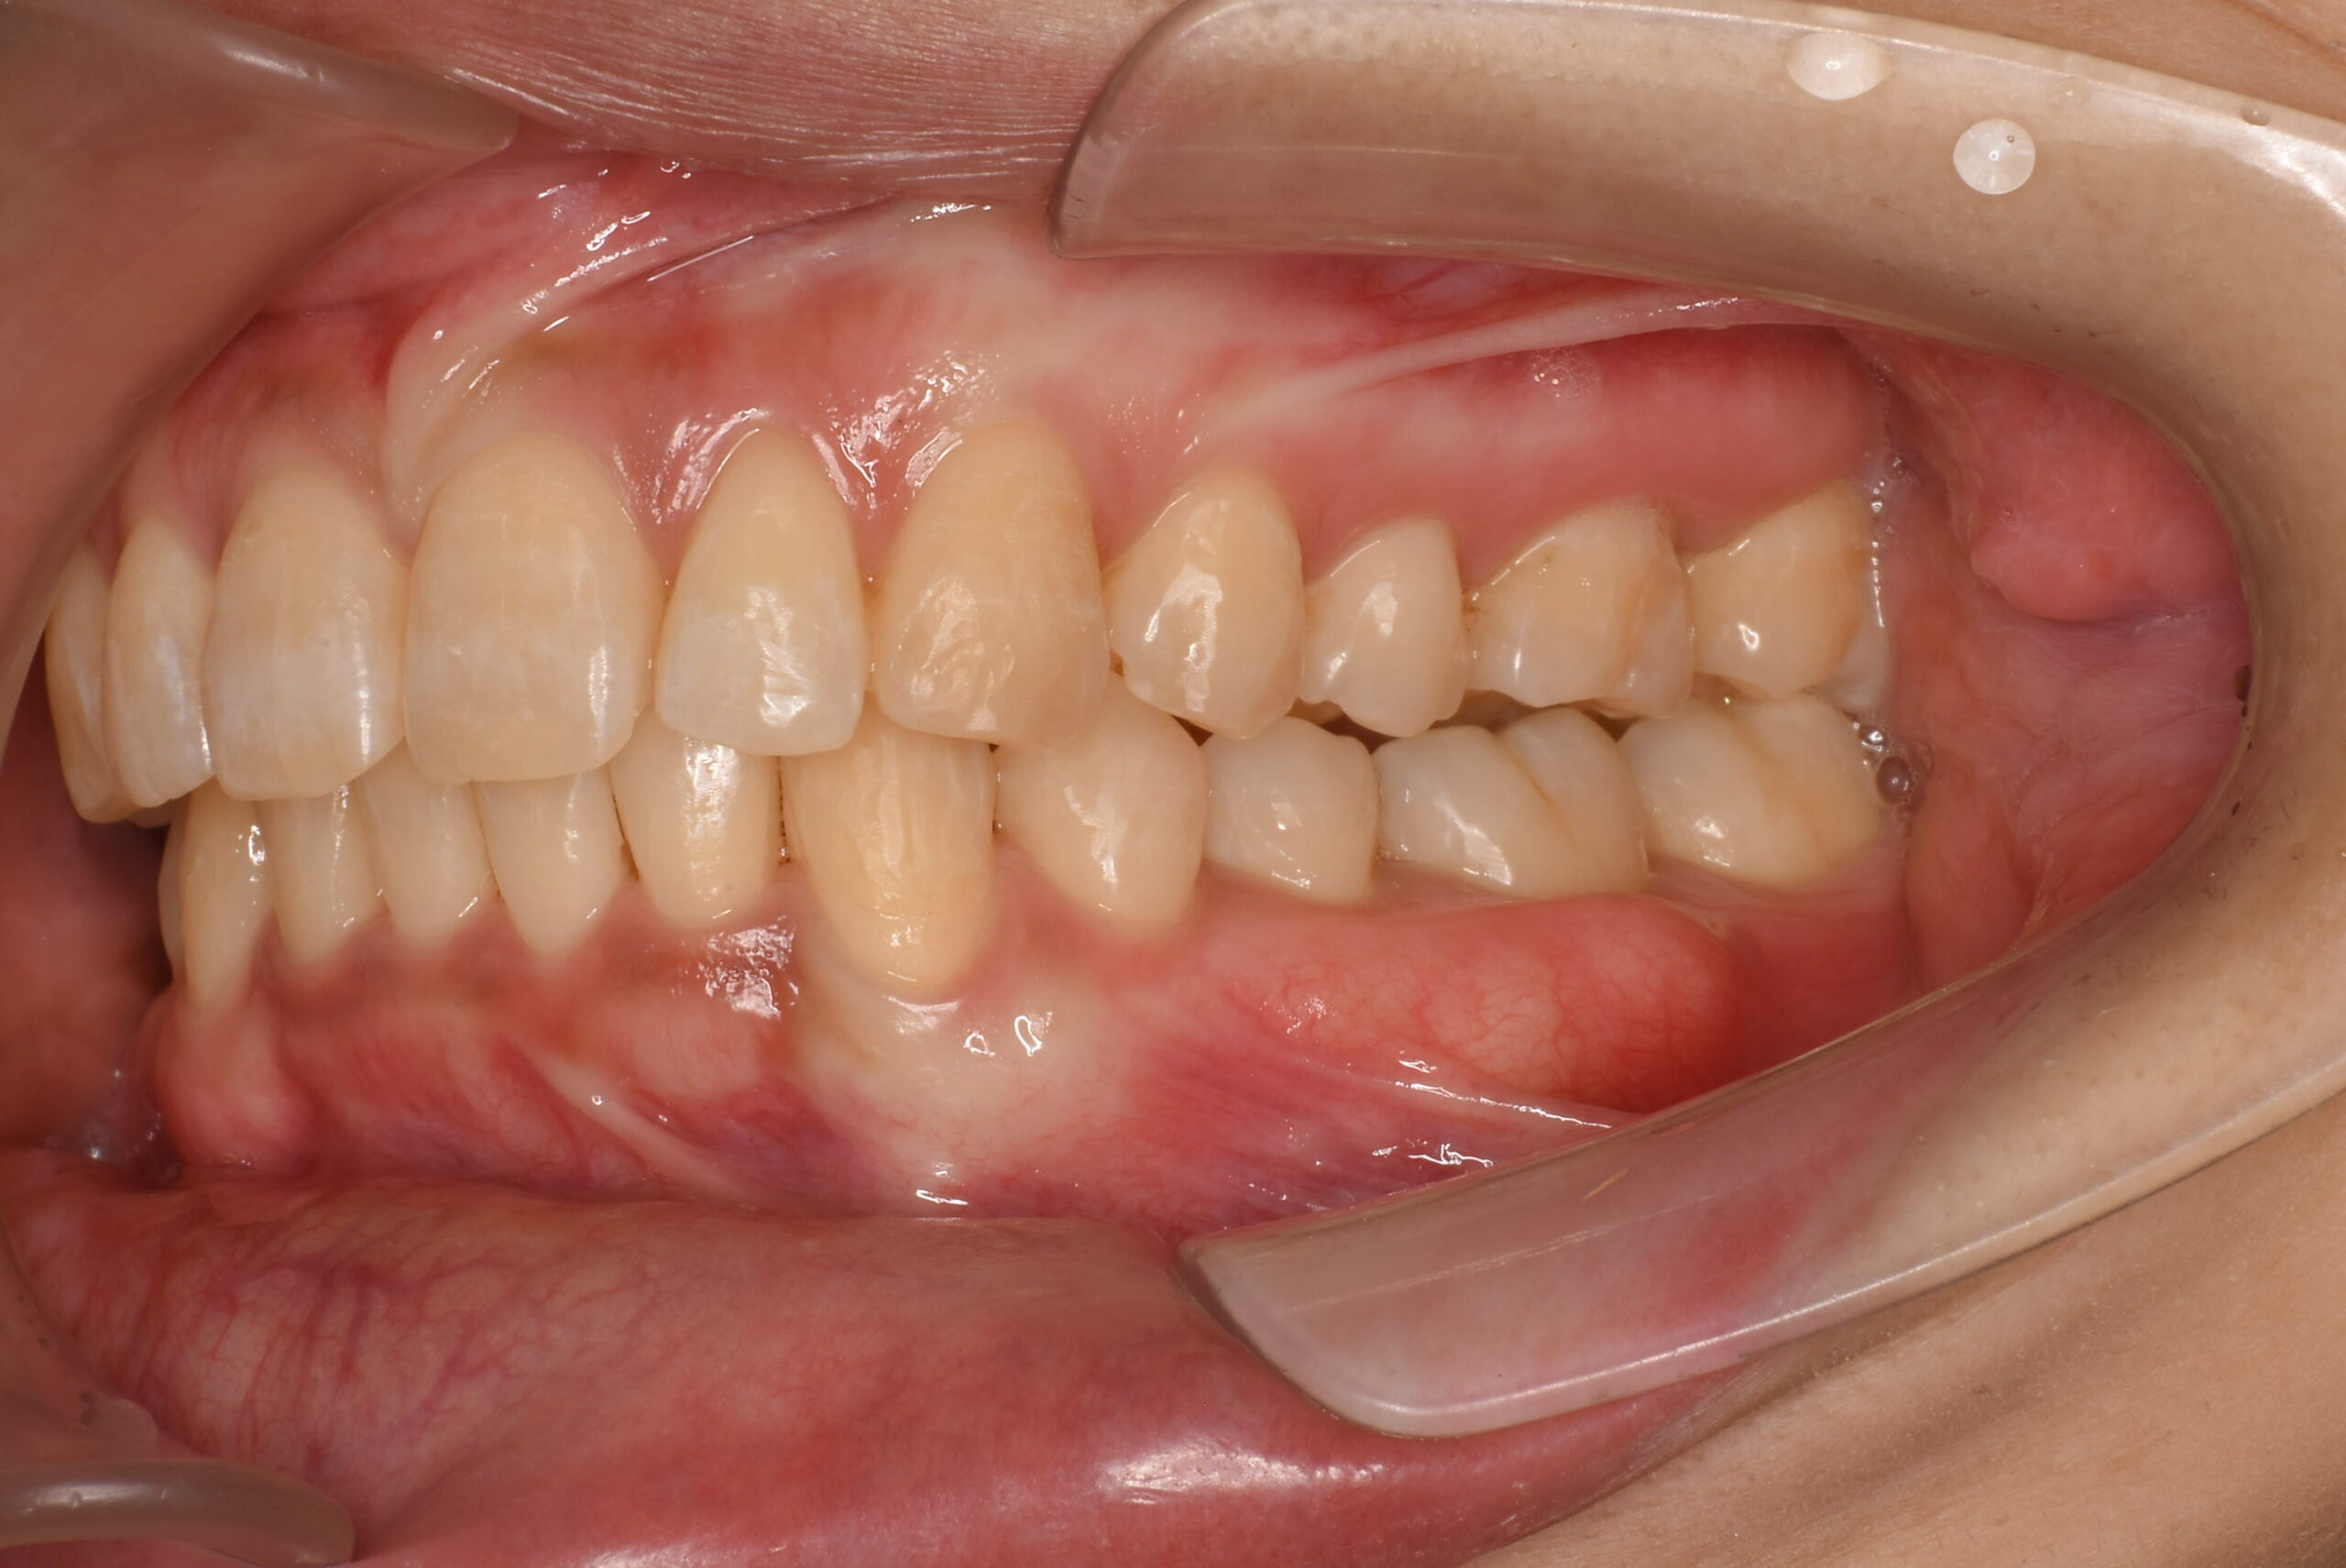

- AFTER

治療後_左側方

| 治療内容 | 患者様は、上下顎前歯部の叢生(歯のガタつき)や歯間空隙(すきっ歯)、前歯の唇側傾斜(前突/出っ歯)を主訴に来院されました。 診査の結果、抜歯を行わずに歯列全体の配列改善が可能と判断し、マウスピース型矯正装置(インビザライン)による非抜歯矯正を計画しました。 初診時には歯周病の初期症状である、歯肉の炎症および出血傾向が認められたため、矯正治療と並行して歯周治療(プラークコントロール・スケーリング)を実施し、口腔衛生環境の改善にも取り組みました。 |

| 治療期間/通院回数 | 19ヶ月 |